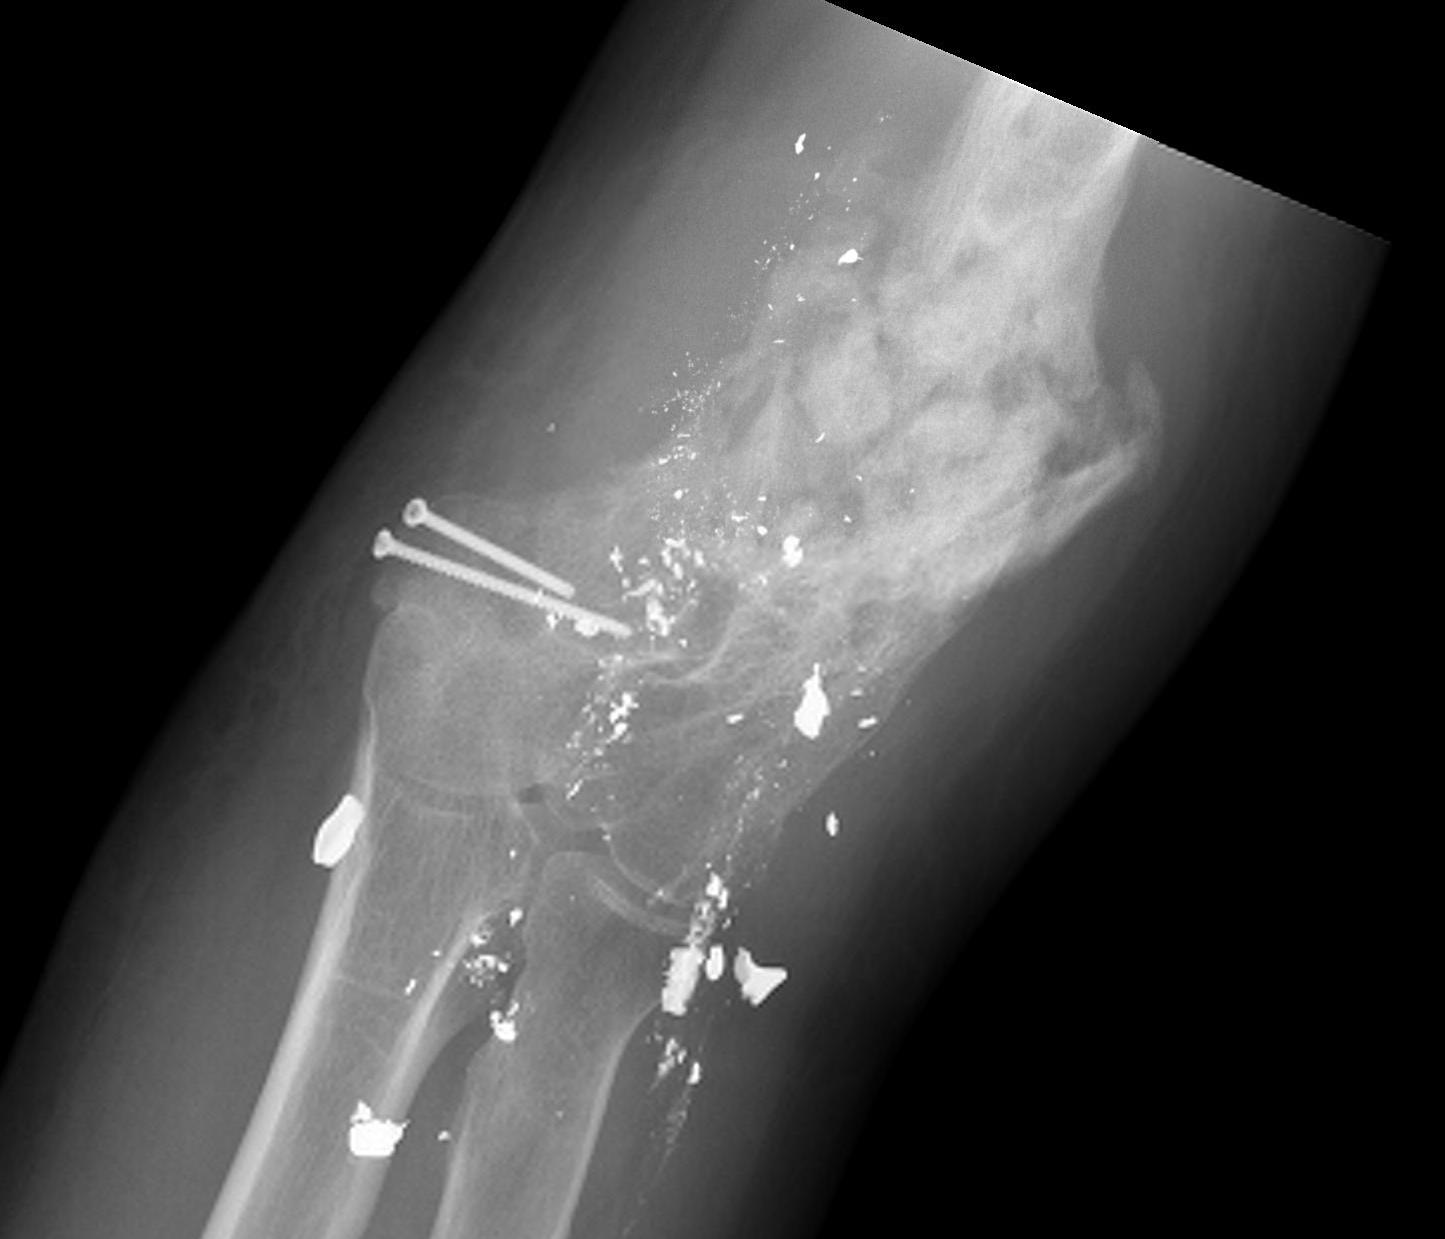

Gunshot wound elbowGunshot wound elbow 2